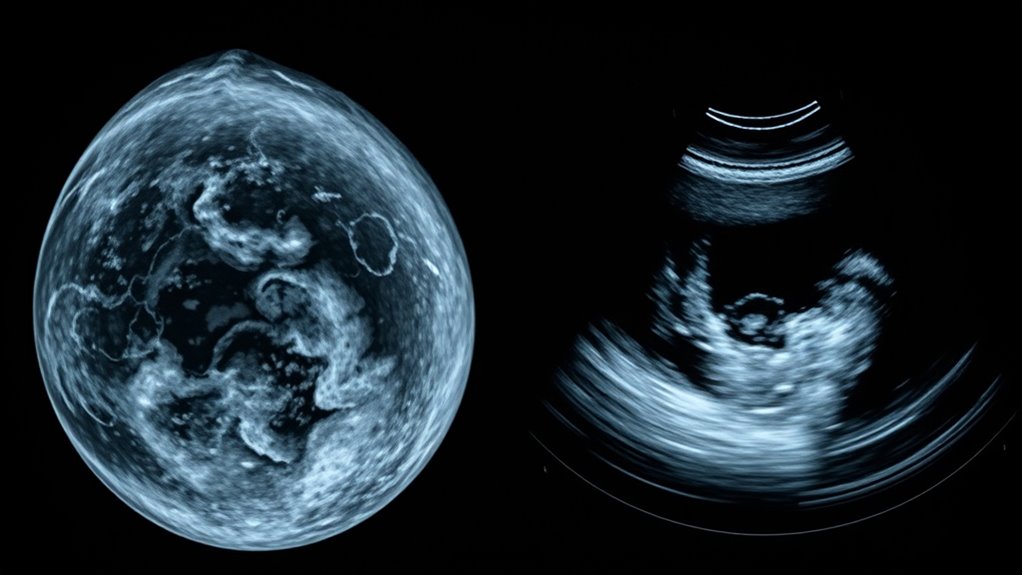

Neue Bildgebungstechniken: 3D-Mammographie, Ki-67-Bewertung & mehr

Fortschritte in der Brustbildgebung

Optimierung der Brustkrebsfrüherkennung durch fortschrittliche Bildgebung und Biomarker wie Ki-67 eröffnet neue Möglichkeiten – erfahren Sie, wie diese Innovationen Ihre Gesundheitsreise beeinflussen können.

Grenzen der Mammographie und Sonographie: Wann Ergebnisse täuschend sein können

Einschränkungen der Mammographie und Ultraschall

Richtlinien zeigen, wann Mammographie und Sonographie täuschen können, und regen die Leser dazu an, Strategien für eine genaue Brustkrebsdiagnose zu erkunden.

Bildgebung: Wie Radiologen gutartige Befunde von Krebs unterscheiden

Radiologen unterscheiden zwischen benignen und bösartigen Tumoren

Über den Blick auf die Oberfläche hinaus nutzen Radiologen Bildgebungsmerkmale und Klassifikationssysteme, um gutartige von bösartigen Befunden zu unterscheiden – entdecken Sie, wie Fachwissen und Technologie eine genaue Diagnose ermöglichen.